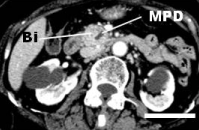

A 78-year-old Japanese woman with a past history of cerebellar infarction complained of appetite loss and general fatigue. She was referred to the National Defense Medical College Hospital (Saitama, Japan), because of jaundice and dilatation of the common bile duct (revealed in an imaging study at a local hospital). Laboratory data revealed elevations in serum bilirubin (direct-bilirubin predominant), aspartate transaminases, alanine transaminases, alkaline phosphatase, -glutaryl transpeptidase, and carbohydrate antigen 19-9, while the serum values of carcinoembryonic antigen and Span-1were within normal limits. Serum squamous cell carcinoma (SCC) antigen was not evaluated. Imaging studies revealed luminal stricture and wall irregularity in the inferior bile duct, with dilatation of both the upstream bile duct and the main pancreatic duct (Figure 1). Although repeated bile cytology failed to confirm malignancy, a pancreaticoduodenectomy was planned with a pre-operative diagnosis of pancreatic or bile duct cancer without distant metastases. However, during the operation a small nodule was found within the pouch of Douglas. Unexpectedly, intraoperative pathologic examination revealed it to be a metastatic deposit of SCC. Pelvic examination revealed a cauliflower-like tumor of the uterine cervix, and histology confirmed it to be SCC, papillary variant. We considered the patient to have both a biliary or pancreatic cancer and stage IIIa cervical cancer, and the pancreaticoduodenectomy was completed. She received best-supportive care for a stage IVb cervical cancer. She died 10 months after the operation. An autopsy was not performed.

Figure 1. Abdominal computed tomography revealed obstruction of the inferior bile duct (Bi). Dilatation of the upstream main pancreatic duct (MPD) also seen. Scale indicated 3 cm